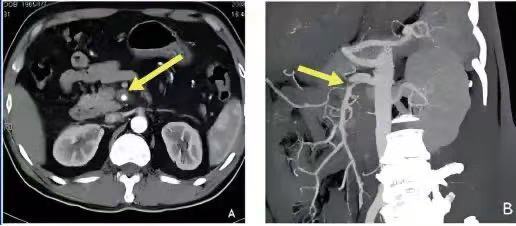

2、CT增强扫描检查(腹部CTA)技术对肠系膜血管栓塞诊断的特异性和敏感性可高达到100%和73%。发现肠系膜上动脉血管管腔充盈缺损或血流中断、肠壁增厚、肠壁扩张伴随气液平面等。是确诊肠系膜上动脉栓塞的主要检查手段。

箭头(黄色)所示暗色部分是肠系膜上动脉血栓。

肠系膜上动脉(左图绿色部分),肠系膜上动脉内血栓(红色箭头)。